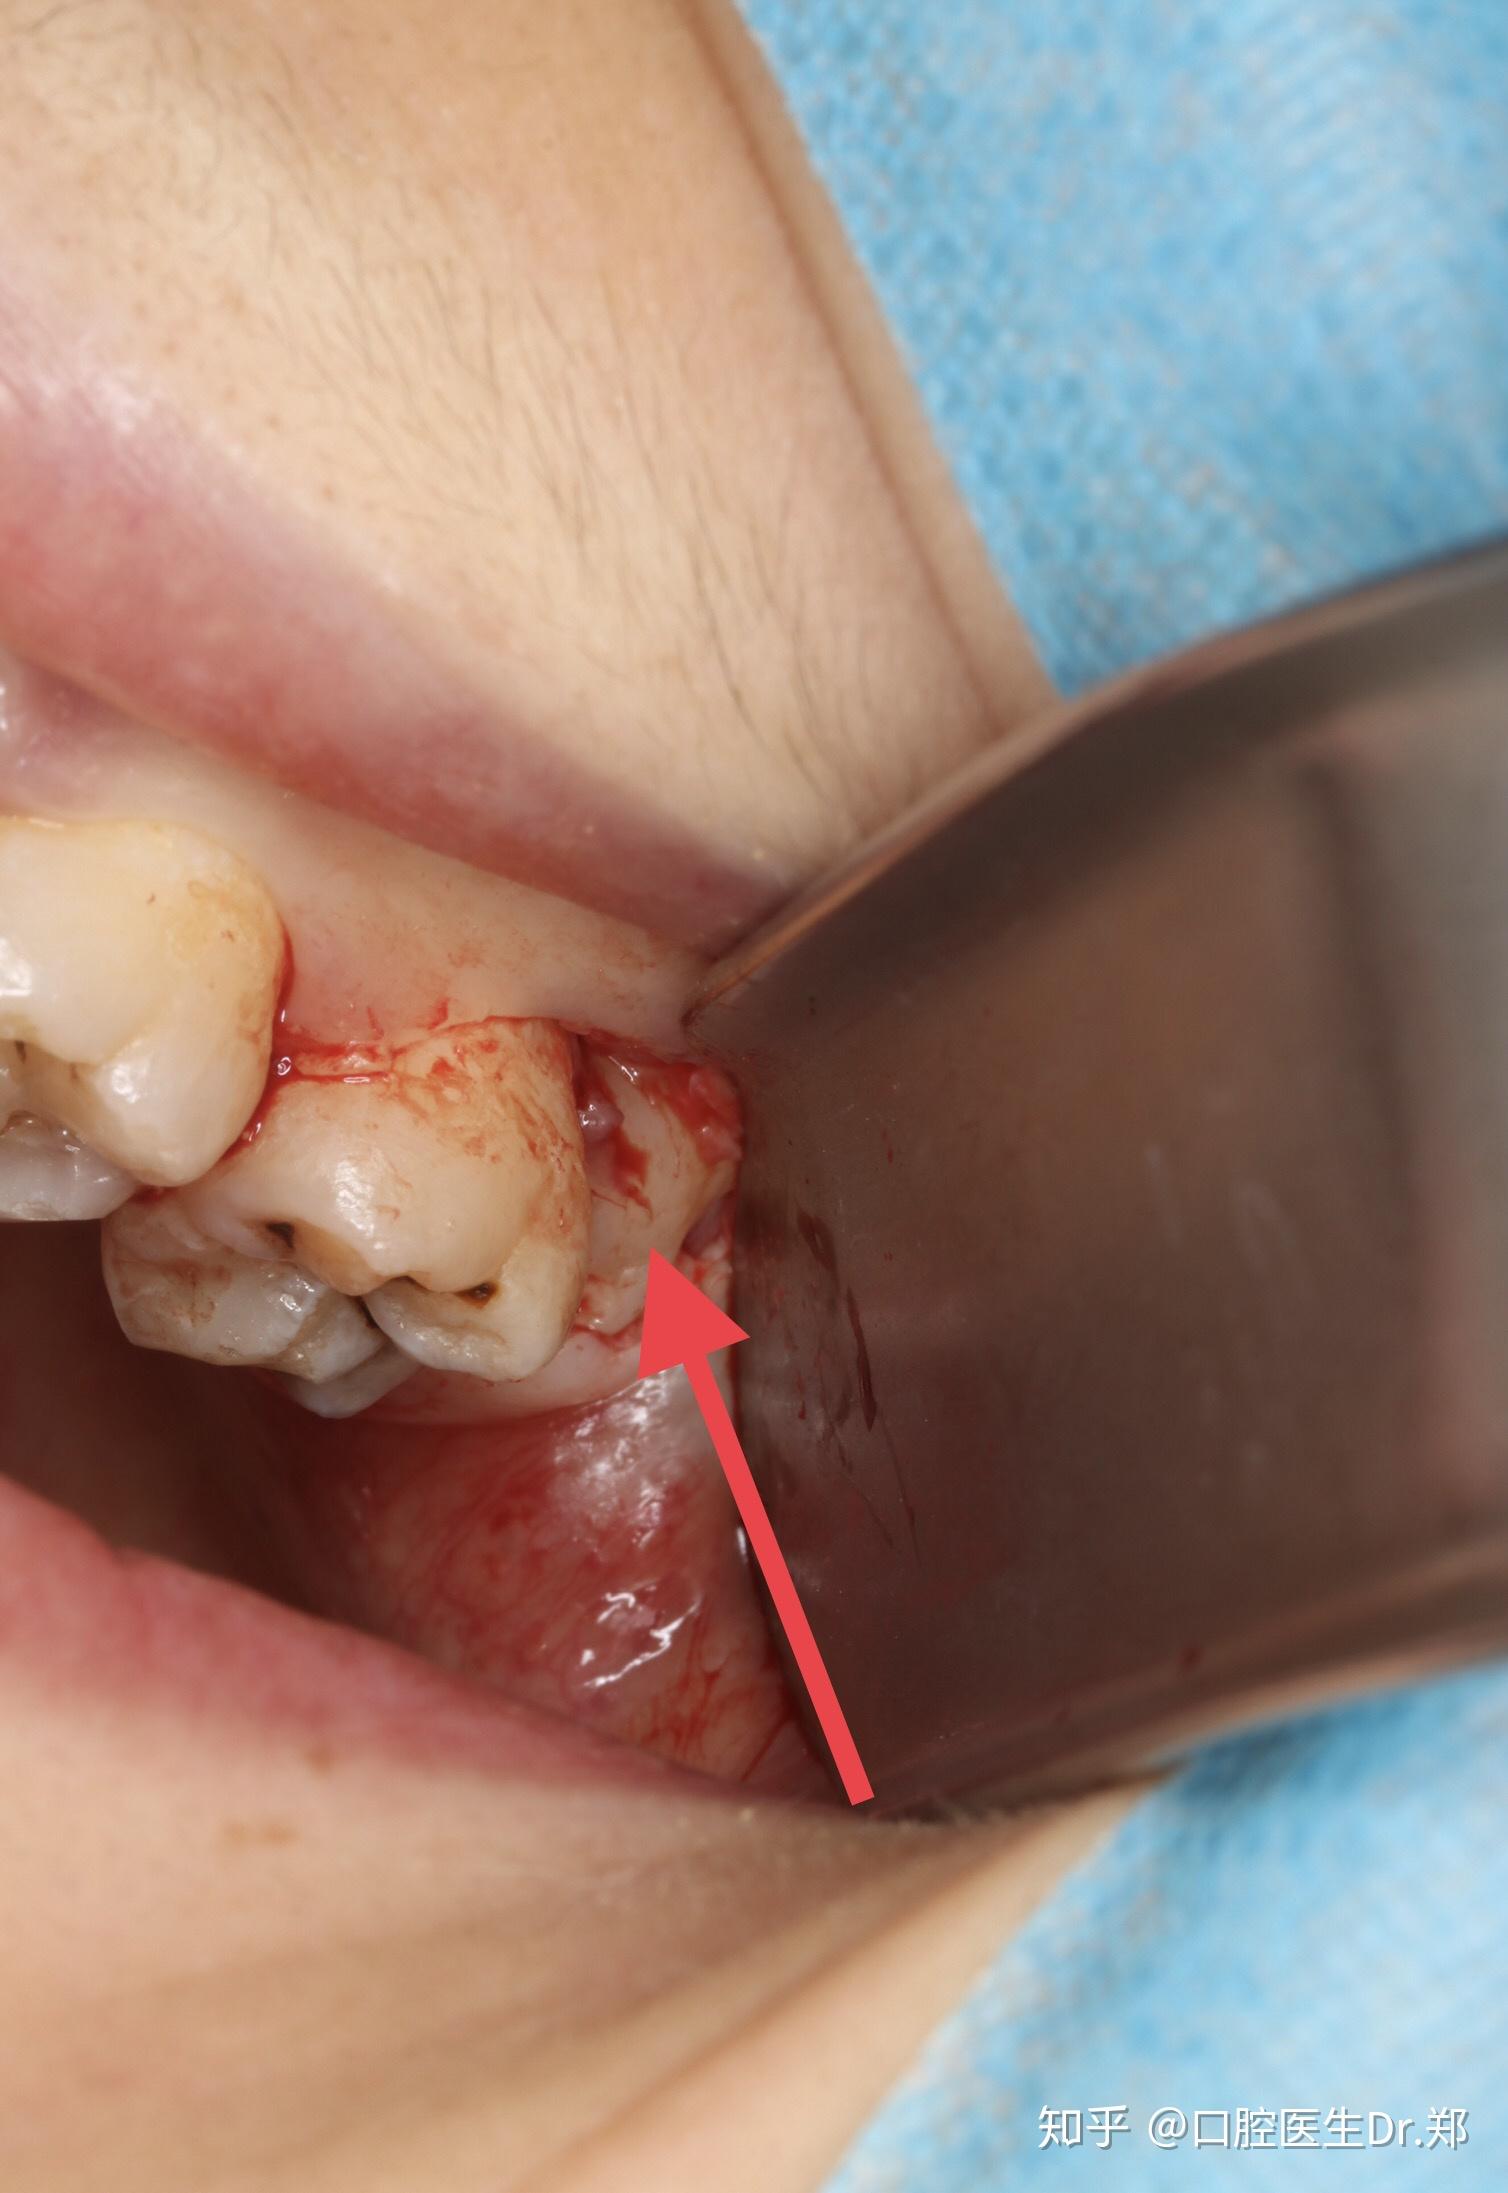

下颌智齿拔除一例

图片尺寸1620x1080